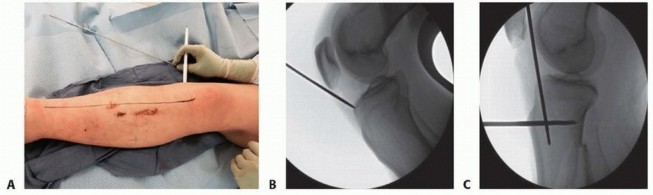

### FIG 4 • Clinical and fluoroscopic examples demonstrating usage of a guidewire to determine tibial anatomic axis and appropriate start site. A. Guidewire placed along tibial crest. B. Correlating fluoroscopic AP view showing guidewire at the medial aspect of the lateral tibial spine. Lateral parapatellar Fractures at the transition between metaphysis and diaphysis The lateral parapatellar approach allows for guidewire and nail placement in the more lateral position, which is beneficial in countering the valgus deformity associated with these fractures. It also allows intramedullary nailing in the familiar hyperflexed knee position. The semiextended position assists for reduction of the flexion deformity associated with these fractures. The limited or formal medial parapatellar may be used if the surgeon is unfamiliar with the suprapatellar approach and special instrumentation is not available. If the suprapatellar approach is being performed, a superomedial or superior midline is used and special instrumentation is required. All of the surgical approaches are performed with the knee in the semiextended position. 553 ## TECHNIQUES -

** Surgical Approach ### Medial Parapatellar Tendon Approach Palpate and mark the medial border of the patellar tendon ( TECH FIG 1, line A). Incise the skin at the medial border of the patellar tendon. Full-thickness skin flaps are developed. Dissection is carried down to the retinaculum. The retinaculum is then split, and the patellar tendon is retracted laterally. Do not incise the capsule. ### Transpatellar Tendon Approach Palpate and mark the medial and lateral border of the patellar tendon, the inferior border of the patella, and the tibial tubercle ( TECH FIG 1, line B). Incise the skin starting at the inferior margin of the patella and continue distally in the middle of the patellar tendon. Full-thickness skin flaps are developed. Incise the paratenon in the midline, and elevate medial and lateral flaps to identify the margins of the patellar tendon. Make a single full-thickness incision in the midline of the patellar tendon. Do not incise the capsule and avoid injuring the menisci at the inferior margin of the incision. ### Lateral Parapatellar Tendon Approach Palpate and mark the lateral border of the patellar tendon ( TECH FIG 1, line C). Incise the skin at the lateral border of the patellar tendon. Full-thickness skin flaps are developed. Dissection is carried down to the retinaculum. The retinaculum is then split, and the patellar tendon is retracted medially. Do not incise the capsule. ### Semiextended Position 26 Medial Parapatellar Approach Either a standard midline or limited medial skin incision can be used ( TECH FIG 2). Full-thickness skin flaps are developed. The distal portion of the quadriceps tendon is incised, leaving a 2-mm cuff of tendon medially for later repair. A formal medial arthrotomy is done extending around the patella, leaving a 2-mm cuff of capsule and retinaculum for later repair, and continuing along the medial border of the patellar tendon.

--- TECH FIG 1 • Options for surgical incisions in relation to the patella and patellar tendon. Medial parapatellar tendon incision (A). Transpatellar tendon incision (B). Lateral parapatellar tendon (C). Superomedial tendon incision (D). Suprapatellar incision (E).